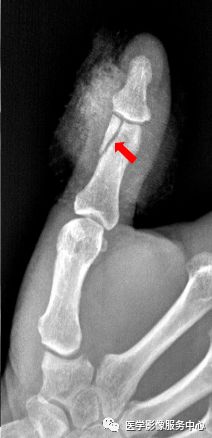

右手中指远节近端背侧关节处见游离骨片影。右手中指远节骨折